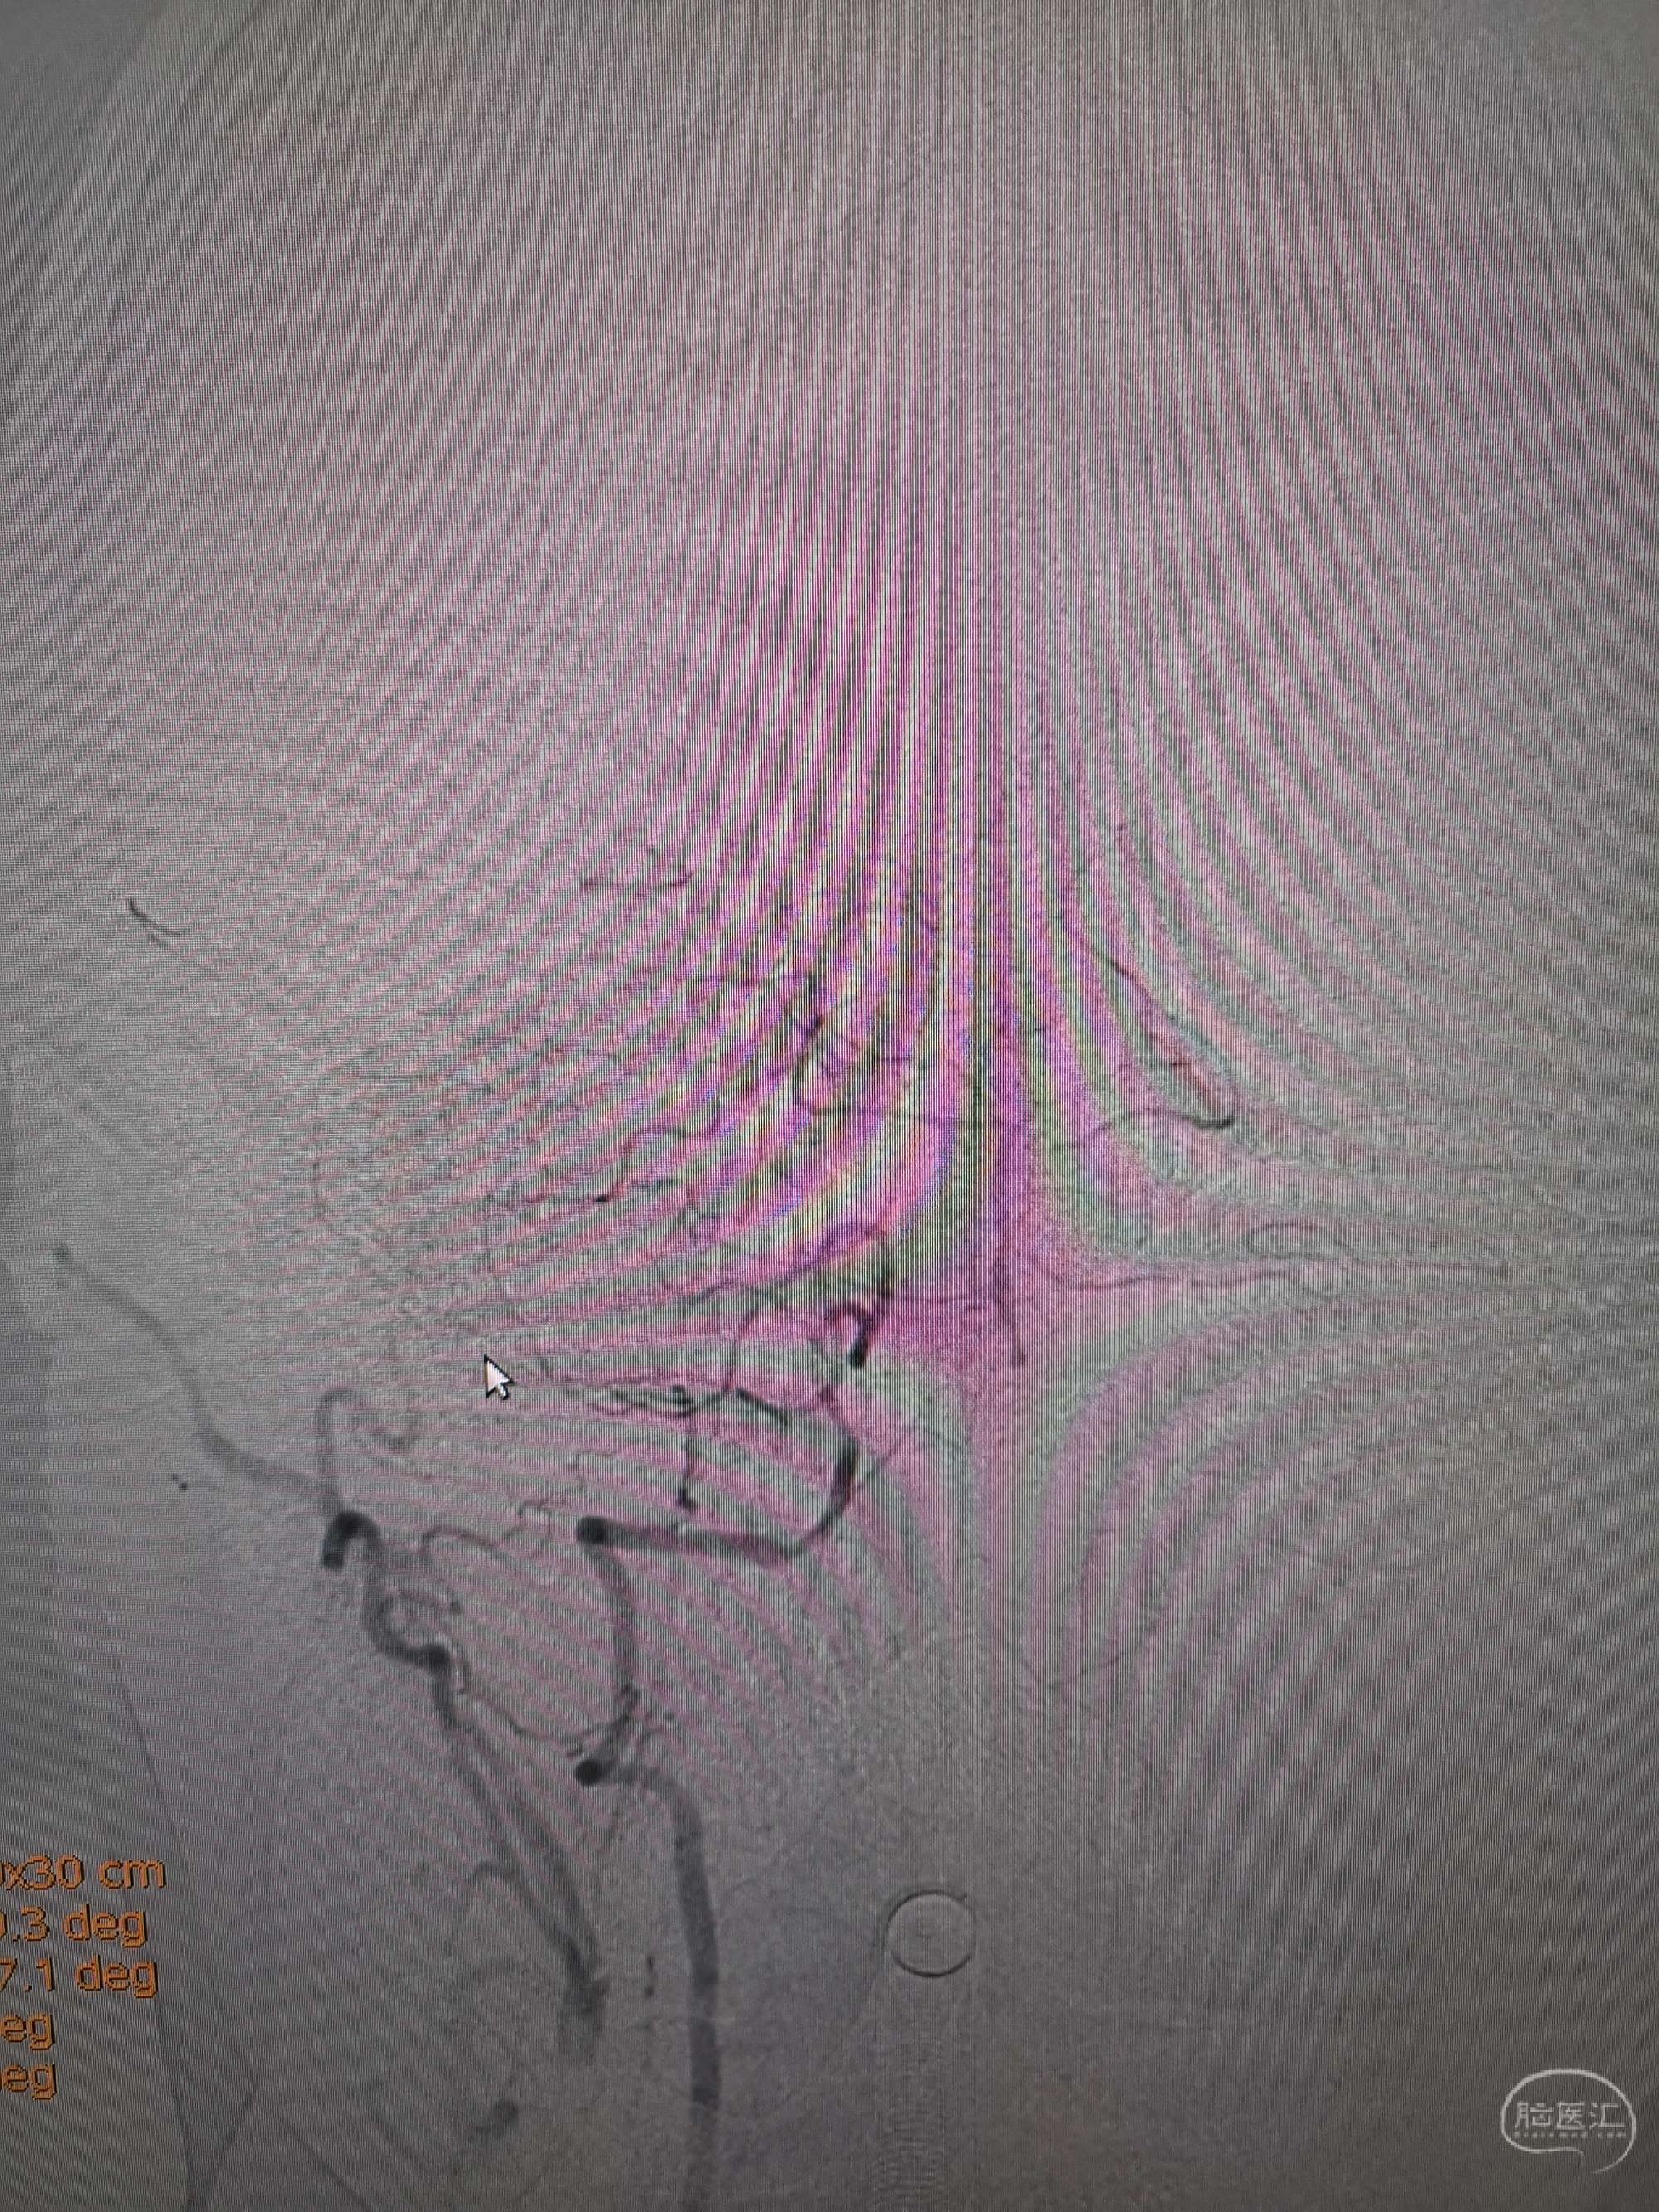

术前再次造影评估

右侧椎动脉穿支供血及左侧PICA供血较入院时略有改善,但改善不明显。故按计划行左侧椎动脉再通术